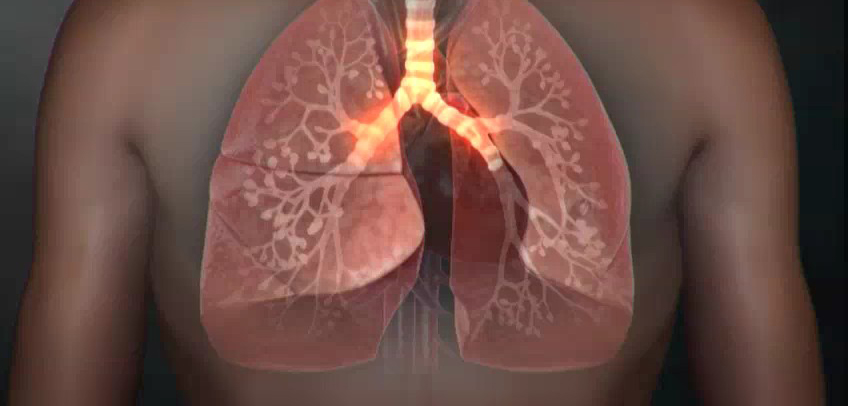

오늘은 단순한 감기와는 달리, 폐에 염증이 생기는 심각한 질환인 폐렴의 증상에 대해 이야기하려 합니다. 폐렴은 세균, 바이러스, 곰팡이 등 다양한 원인에 의해 발생하며, 특히 면역력이 약한 어린이나 노인에게 치명적일 수 있습니다.

- 호흡 곤란 및 가슴 통증

- 설명: 폐렴의 가장 심각하고 중요한 증상입니다. 폐에 염증이 생겨 폐 기능이 떨어지면서 숨쉬기 힘들어지며, 얕고 빠른 호흡을 하게 됩니다. 심한 경우 가슴에 통증을 느끼거나, 옆구리가 결리는 듯한 느낌을 받을 수 있습니다.